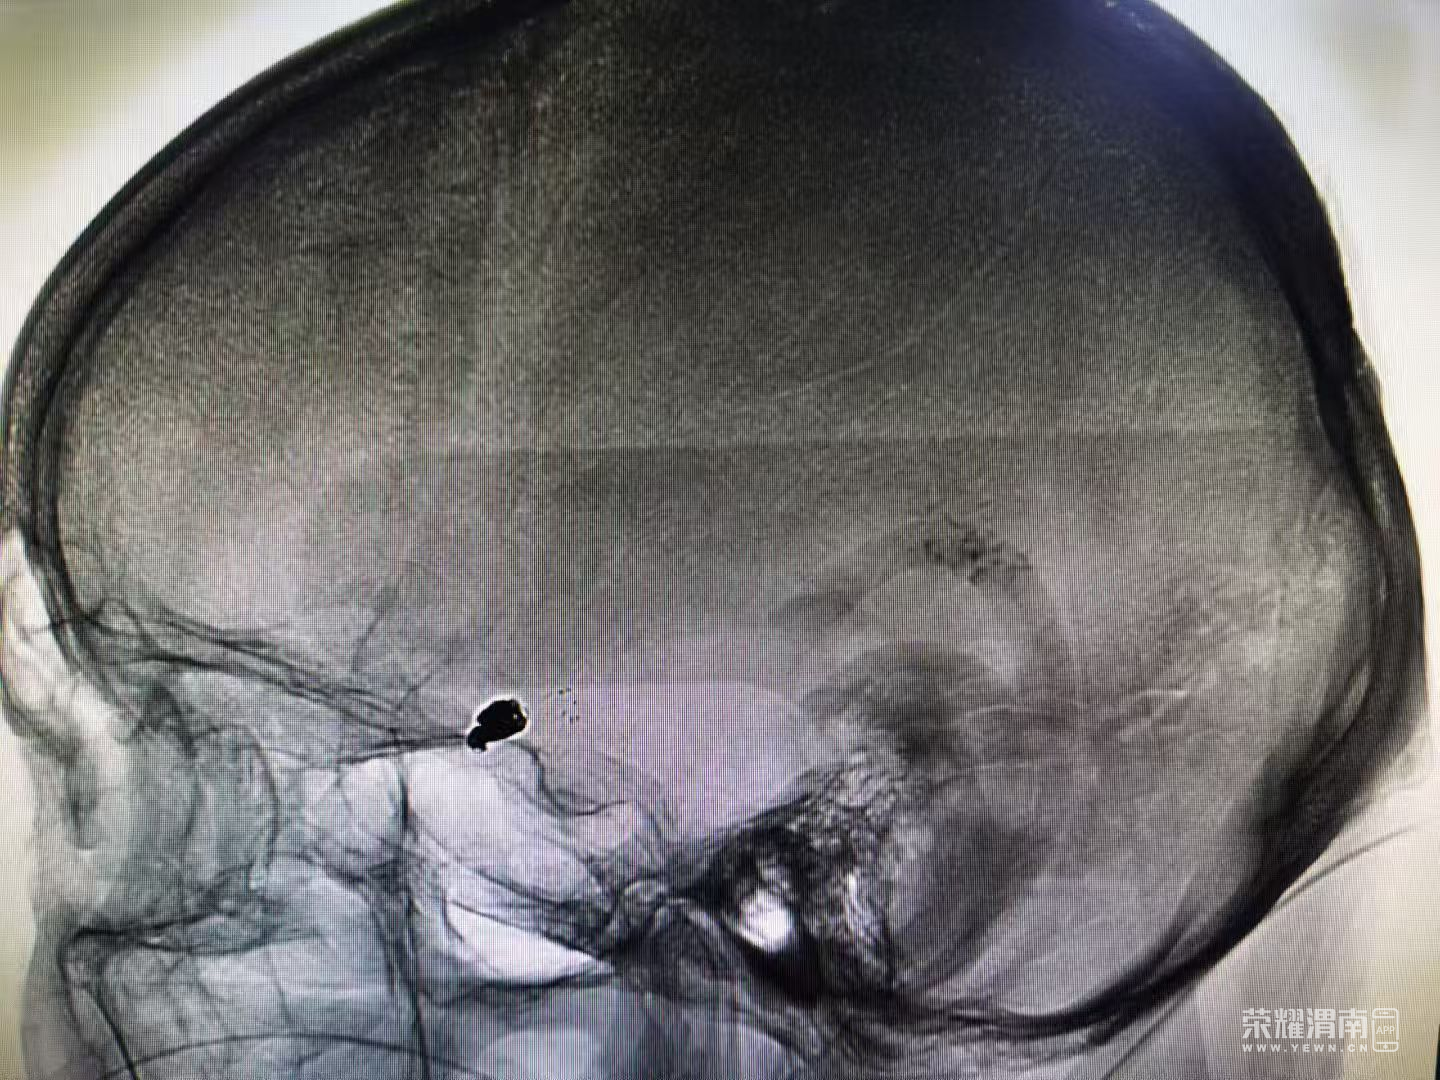

在此基础上,神经外科联合重症医学科、手术麻醉科、介入科组成多学科诊疗小组,通过多次会诊研讨,为患者制定了个体化治疗方案——行动脉瘤支架辅助弹簧圈栓塞术

手术过程中,各科室紧密协作:介入科准确定位动脉瘤,麻醉科全程监测维持生命体征平稳,神经外科顺利完成支架辅助弹簧圈栓塞,成功封闭破裂动脉瘤。术后,重症医学科接力开展全面监护与治疗,帮助患者平稳度过感染期与康复阶段。